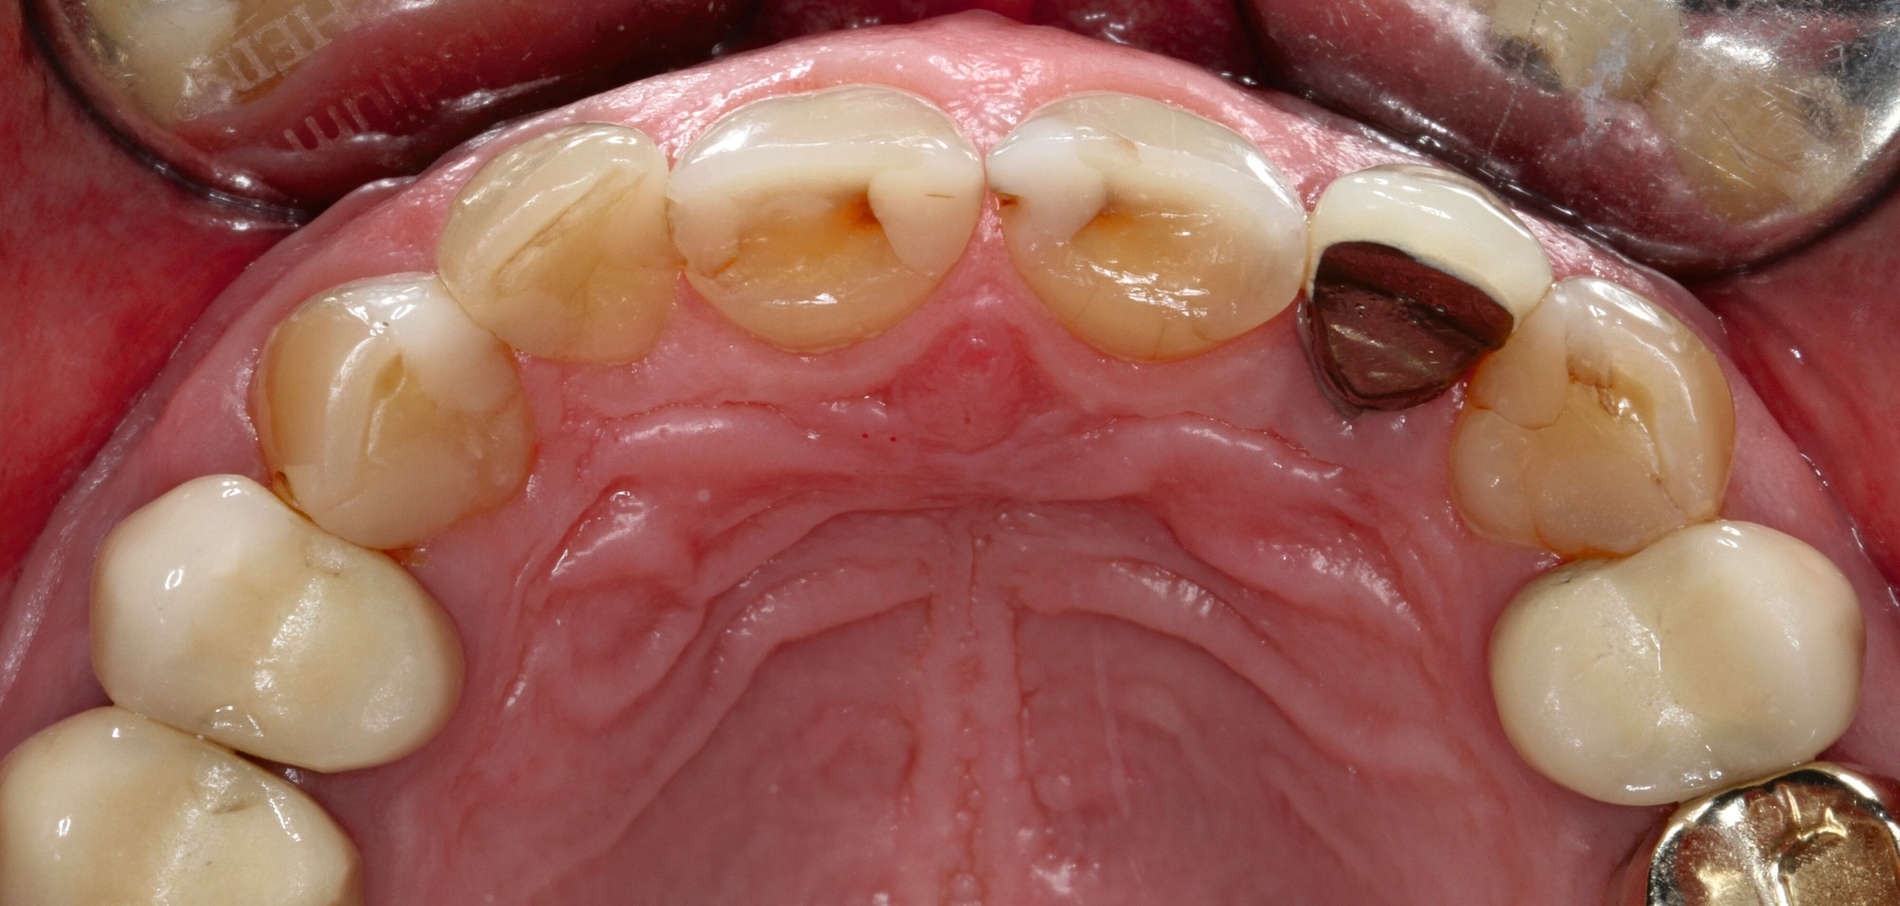

Die dentale Ausgangssituation zeigte im Seitenzahnbereich ein suffizient konservierend und prothetisch versorgtes Gebiss der zweiten Dentition sowie im Frontzahnbereich nicht kariogene Zahnhartsubstanzverluste und eine defekte Krone mit Sekundärkaries (Abbildungen 1 und 2).

Zur Verbesserung der Ästhetik und des Wohlbefindens des Patienten standen die Harmonisierung der Lachlinie und des Frontzahnbogens sowie Farb- und Formkorrekturen der Oberkieferfrontzähne im Fokus. An den Zähnen 11 und 21 waren Zahnhartsubstanzverluste durch Erosion und Attrition zu erkennen. Zahn 23 hatte ebenfalls einen erosiven Defekt, Zahn 13 eine farblich abweichende Kompositrestauration und die Zähne 14 und 24 wiesen keilförmige Defekte zervikal der Kronenränder auf, die einen suffizienten Randschluss haben (Abbildung 1a).

Vor 25 Jahren hatte der Patient ein Frontzahntrauma an Zahn 22 erlitten, der daraufhin mit einer Wurzelspitzenresektion und einer retrograden Amalgamfüllung versorgt worden war (Abbildung 3a). Dabei war die Zahnkrone mit einer keramisch verblendeten Stiftkrone aus Nichtedelmetall rekonstruiert worden, die nun aufgrund von Sekundärkaries insuffizient und gelockert war, jedoch keine Beschwerden verursachte. Klinisch wies der Zahn eine sehr kurze klinische Krone ohne ausreichendes Ferruledesign auf (Abbildung 5a) [Naumann et al., 2018a; Naumann et al., 2018b]. Neben dem Verdacht auf einen obliterierten mittleren Wurzelkanalabschnitt gab es röntgenologisch keinen Hinweis auf apikale Osteolysen oder parodontale Auffälligkeiten (Abbildung 3b). Der Patient entschied sich trotz des erhöhten Zahnhartsubstanzdefekts für den Zahnerhalt durch einen adhäsiv verankerten Kompositaufbau.